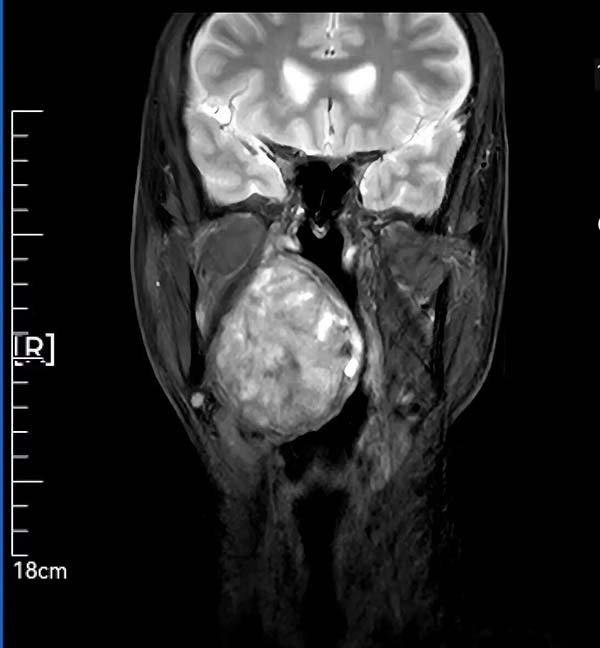

59岁患者因腭部膨隆伴吞咽呼吸困难辗转求医,最终就诊于我院头颈外科。李智林副主任查体发现,患者咽部明显膨隆,悬雍垂左偏,双侧扁桃体完全被肿瘤遮蔽,口咽腔严重狭窄移位。影像检查显示,6.2×1.4×7.3cm的肿瘤深居右侧咽旁间隙,穿刺病理提示,明确为涎腺来源多形性腺瘤,毗邻颈动脉、颅底神经群,手术风险极高。

术前攻坚:利用MRI精准定位肿瘤边界,制定血管神经保护预案;